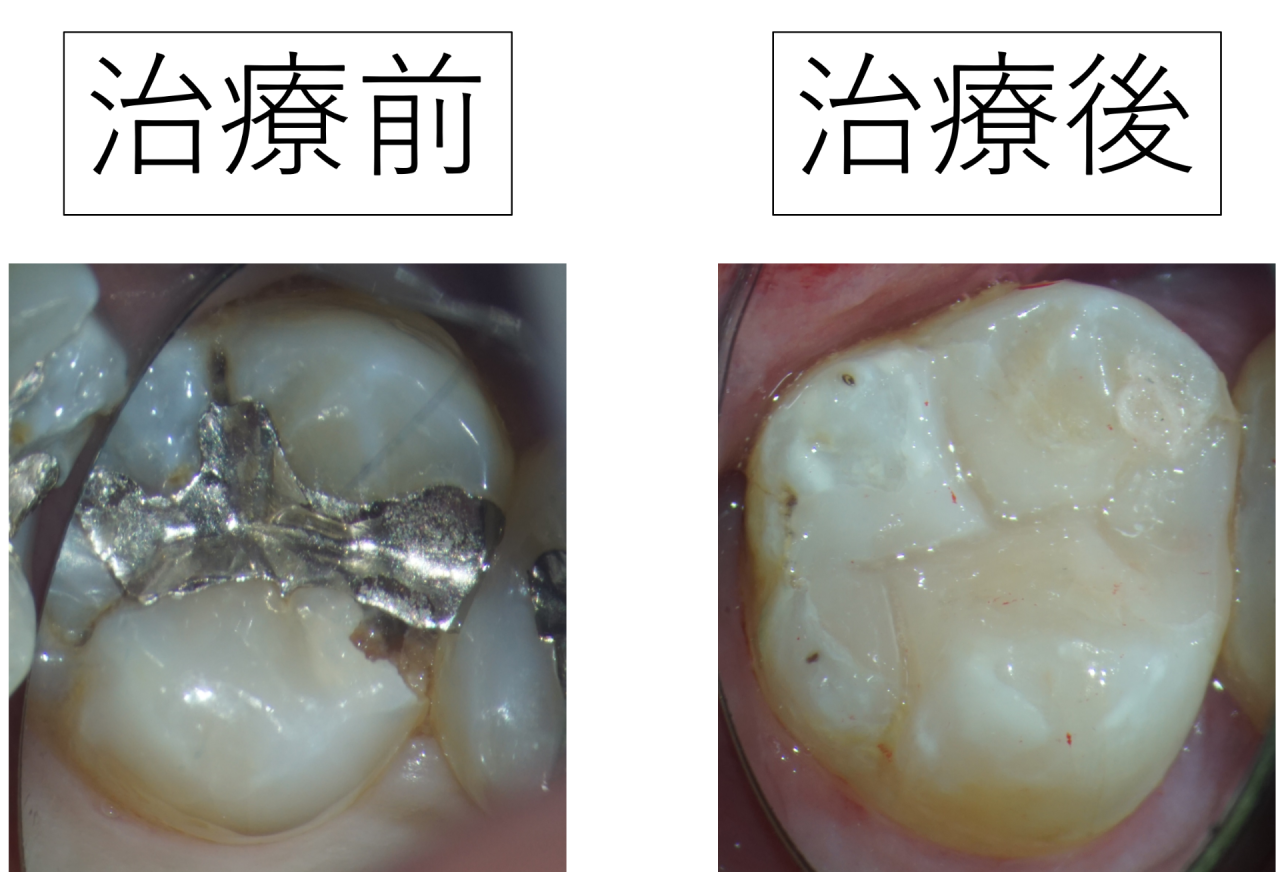

【銀歯は虫歯を作りやすい】銀歯で歯がかけて虫歯ができた奥歯を白いレジンで治しました

今回は、左上の奥歯(上顎第二大臼歯)に入っていた銀歯(メタルインレー)が原因で歯が欠け、そこから虫歯が進んでしまったケースを、写真と合わせてご紹介します。

虫歯を除去し、自然な形に修復した状態

治療後の写真では、

虫歯の部分を丁寧に取り除き、失われた形をCRで再現しています。

境目の段差がなくなり、噛み合わせも安定するように調整しました。